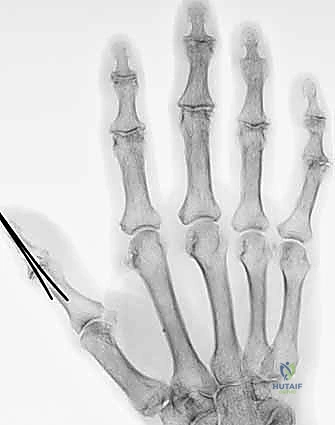

الأساس المتين هو أول خطوة في البناء. يقوم الدكتور هطيف بتقصير العظام قليلاً (Bone Shortening) لتخفيف الشد على الأوعية الدموية والأعصاب عند توصيلها. يتم تثبيت العظام باستخدام أسلاك كيرشنر المعدنية (K-wires)، أو مسامير دقيقة، أو صفائح معدنية صغيرة. التثبيت يجب أن يكون قوياً ليسمح ببدء العلاج الطبيعي المبكر.